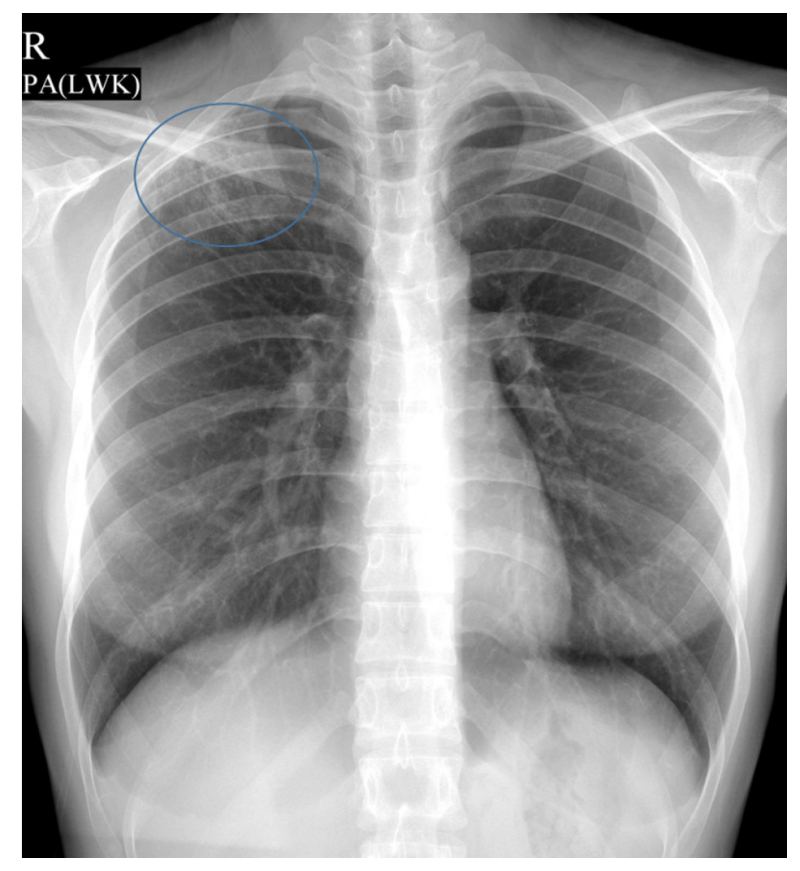

결핵과 폐 사진을 통한 이해

결핵은 주로 폐에 영향을 미치는 병이며, X-ray나 CT를 통해 결핵에 의한 변화를 확인할 수 있습니다. 초기에는 작은 점 같은 병변들이 있을 수 있으며, 진행된 경우에는 폐의 일부가 충혈되거나 손상될 수 있습니다. 이런 이미지는 결핵의 진단과 치료에 매우 중요한 역할을 합니다.